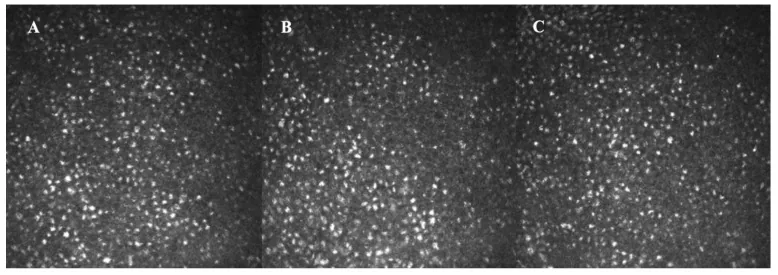

前向き研究:アマンタジン服用患者は角膜内皮細胞密度の減少率が1.51%/年と、非服用PD患者(0.94%)や健常者(0.55%)より大きかった

高用量ほど影響:六角形細胞率の減少と変動係数の上昇が用量依存的に増大した

アマンタジン誘発角膜浮腫で角膜移植が必要となった症例の組織病理検査では、滴状角膜や炎症を伴わない中等度から完全な角膜内皮細胞の消失が認められた。薬剤誘発性のストレスが角膜内皮細胞に加わり、閾値を超えると内皮細胞の機能不全および消失が進行し、ポンプ機能の低下により角膜間質に水分が貯留して浮腫が生じると推定されている。

ヒトの角膜内皮細胞は再生能力がほとんどなく、障害を受けた細胞は周囲の細胞が扁平化して面積を拡大することで補われる。アマンタジン中止後に角膜浮腫が消失しても内皮細胞密度は低値のまま残ることが多く、将来的な角膜代償不全のリスクを抱える。このため長期フォローアップが推奨される。